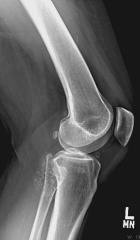

42 year old female with one month of knee pain

Zoom image: Radiological image Radiological image.